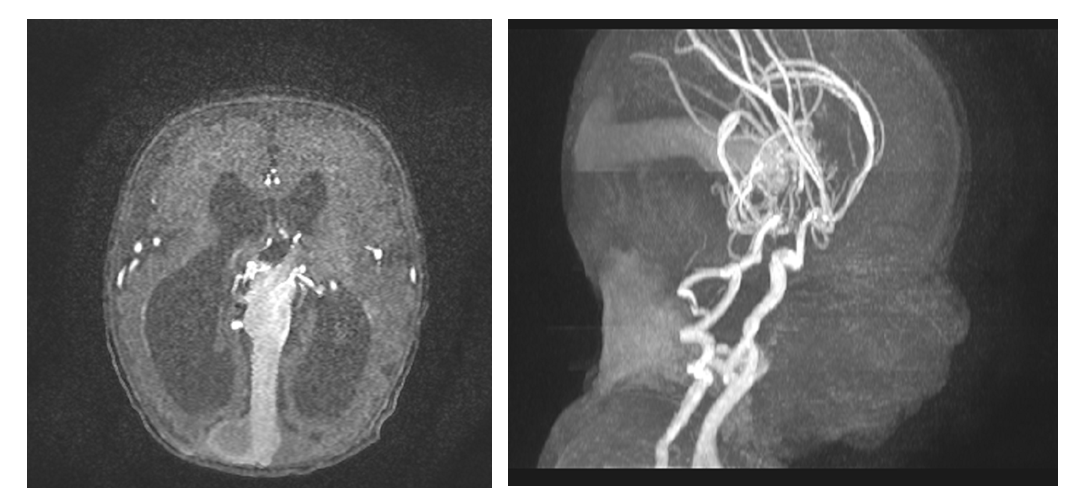

A Vein of Galen aneurysmal malformation was noted due to multiple arterial feeders including the thalamoperforating, choroidal and pericallosal arteries converging at its anterior aspect with subsequent obstructive hydrocephalus due to posterior compression of the third ventricle and vestibular aqueduct (Figure 1A) (Figure 1B). Head circumference was followed up on a daily basis. It wasn't increasing, on the contrary over the weeks, the head circumference was decreasing. VP shunt was not done since the hydrocephalus is stable and due to the high surgical risk. Repeated echocardiography at day 6 of life showed dilated cardiomyopathy, persistence of the poor right contractility and tricuspid regurgitation but a decrease in the pulmonary hypertension to 40 mmHg. So NO was stopped, spirolactone was started and furosemide was tapered to 0.5mg 12h. Patient was improving; however his bilirubin level was on the rise (indirect hyperbilirubinemia). Therefore, an abdominal ultrasound with Doppler to look for other malformations was ordered. It revealed no hepatomegaly, no abdominal aortic aneurysm, normal kidneys size with no aneurysms involving the renal vessels.